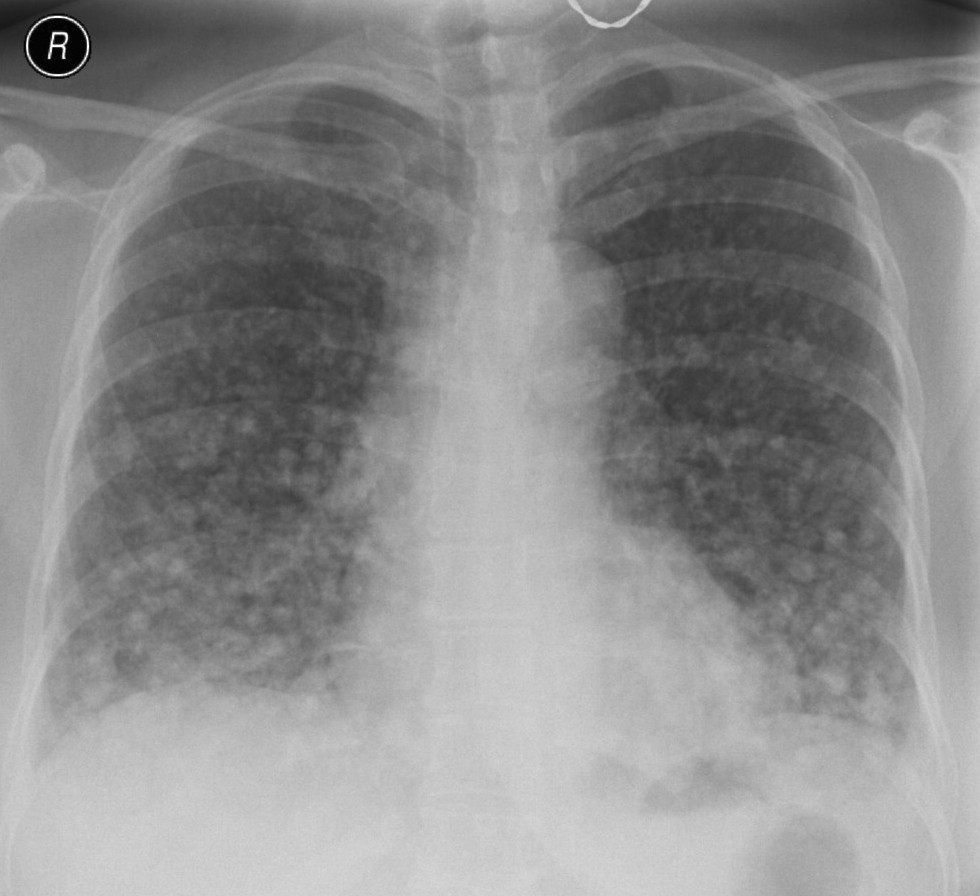

20. Miliary lung metastases. HRCT, coronal reconstruction:

60 year old man, secondary pulmonary lesions due to kidney tumor, underwent target therapy.

Lobulated nodule in the left lung, associated with the pleura dorsobasally.

Lobectomy because of right lung adenocarcinoma, (brain metastasis). (by the contribution of Zsuzsanna Monostori, MD, PhD)